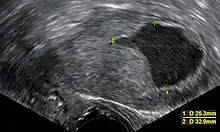

- Accumulation of fluids other than blood or of unknown constitution. One study came to the conclusion that postmenopausal women with endometrial fluid collection on gynecologic ultrasonography should undergo endometrial biopsy if the endometrial lining is thicker than 3 mm or if the endometrial fluid is echogenic. In cases of a lining 3 mm or less and clear endometrial fluid, endometrial biopsy was not regarded to be necessary, but endocervical curettage to rule out endocervical cancer was recommended.[25]